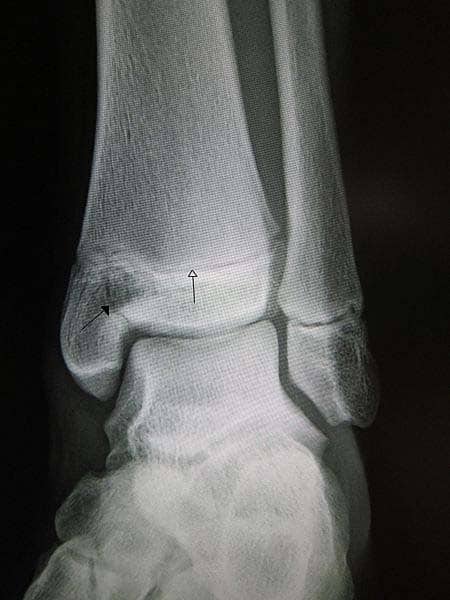

The tibia is the main bone of the lower leg, forming what is more commonly known as the shin. It expands at its proximal and distal ends; articulating at the knee and ankle joints respectively. The tibia is the second largest bone in the body and it is a key weight-bearing structure. In this article, we shall look at anatomy of the tibia – its bony landmarks, articulations and clinical correlations. By Anatomography [CC-BY-SA-2.1-jp], via Wikimedia Commons Fig 1Overview of the tibia in the human skeleton Pro Feature - 3D Model You've Discovered a Pro Feature Access our 3D Model Library Explore, cut, dissect, annotate and manipulate our 3D models to visualise anatomy in a dynamic, interactive way. Learn More Proximal The proximal tibia is widened by the medial and lateral condyles, which aid in weight-bearing. The condyles form a flat surface, known as the tibial plateau. This structure articulates with the femoral condyles to form the key articulation of the knee joint. Located between the condyles is a region called the intercondylar eminence – this projects upwards on either side as the medial and lateral intercondylar tubercles. This area is the main site of attachment for the ligaments and the menisci of the knee joint. The intercondylar tubercles of the tibia articulate with the intercondylar fossa of the femur. By TeachMeSeries Ltd (2025) Fig 2The tibial plateau. The tibial condyles articulate with the femoral condyles to form the knee joint. Shaft The shaft of the tibia is prism-shaped, with three borders and three surfaces; anterior, posterior and lateral. For brevity, only the anatomically and clinically important borders/surfaces are mentioned here. Anterior border – palpable subcutaneously down the anterior surface of the leg as the shin. The proximal aspect of the anterior border is marked by the tibial tuberosity; the attachment site for the patella ligament. Posterior surface – marked by a ridge of bone known as soleal line. This line is the site of origin for part of the soleus muscle, and extends inferomedially, eventually blending with the medial border of the tibia. There is usually a nutrient artery proximal to the soleal line. Lateral border – also known as the interosseous border. It gives attachment to the interosseous membrane that binds the tibia and the fibula together. By TeachMeSeries Ltd (2025) Fig 3Bony landmarks of the tibial shaft. Clinical Relevance Intraosseous Access Intraosseous access is a form of vascular access used in the emergency setting. It allows the administration of fluids, blood products and medications directly into the bone marrow. IO access is typically used in an emergency when intravenous access is not obtainable. There are two main sites in the tibia that are suitable for IO access: Anteromedial surface, 2-3cm below the tibial tuberosity Proximal to the medial malleolus Complications of IO access include osteomyelitis, iatrogenic fracture and compartment syndrome. IO infusions should be discontinued when IV access has been achieved. Distal The distal end of the tibia widens to assist with weight-bearing. The medial malleolus is a bony projection continuing inferiorly on the medial aspect of the tibia. It articulates with the tarsal bones to form part of the ankle joint. On the posterior surface of the tibia, there is a groove through which the tendon of tibialis posterior passes. Laterally is the fibular notch, where the fibula is bound to the tibia – forming the distal tibiofibular joint. Clinical Relevance Fractures of the Tibia Fractures of the tibia are relatively common. There are two main types: High energy trauma – occurs predominantly in the younger population. Low energy trauma or insufficiency fractures – occurs predominantly in the elderly. Fractures most commonly occur at the shaft of the tibia, and are typically associated with fibula fractures. Fractures of the proximal tibia are known as tibial plateau fractures; the condyles may be broken and injury to the menisci and ligaments of the knee is not uncommon. These fractures are classified using the Schatzker classification, and if very displaced will likely required operative management. It is important to monitor patients for signs of compartment syndrome in the pre-and post-operative phases. At the ankle, the medial malleolus can be fractured. This is caused by the ankle being twisted inwards (over-inversion) – the talus of the foot is forced against the medial malleolus, causing a spiral fracture. This rarely happens in isolation and typically the lateral malleolus is also fractured; potentially producing an unstable fracture that requires operative management. By James Heilman, MD [CC-BY-SA-3.0], via Wikimedia Commons Fig 4Fracture of the medial malleolus (black arrow) in a child, with the whiting arrow marking a normal growth plate. This is a Salter Harris type III fracture. Do you think you’re ready? Take the quiz below Pro Feature - Quiz The Tibia Question 1 of 3 Submitting... Skip Next Rate question: You scored 0% Skipped: 0/3 1800 More Questions Available Upgrade to TeachMeAnatomy Pro Challenge yourself with over 1800 multiple-choice questions to reinforce learning Learn More Rate This Article